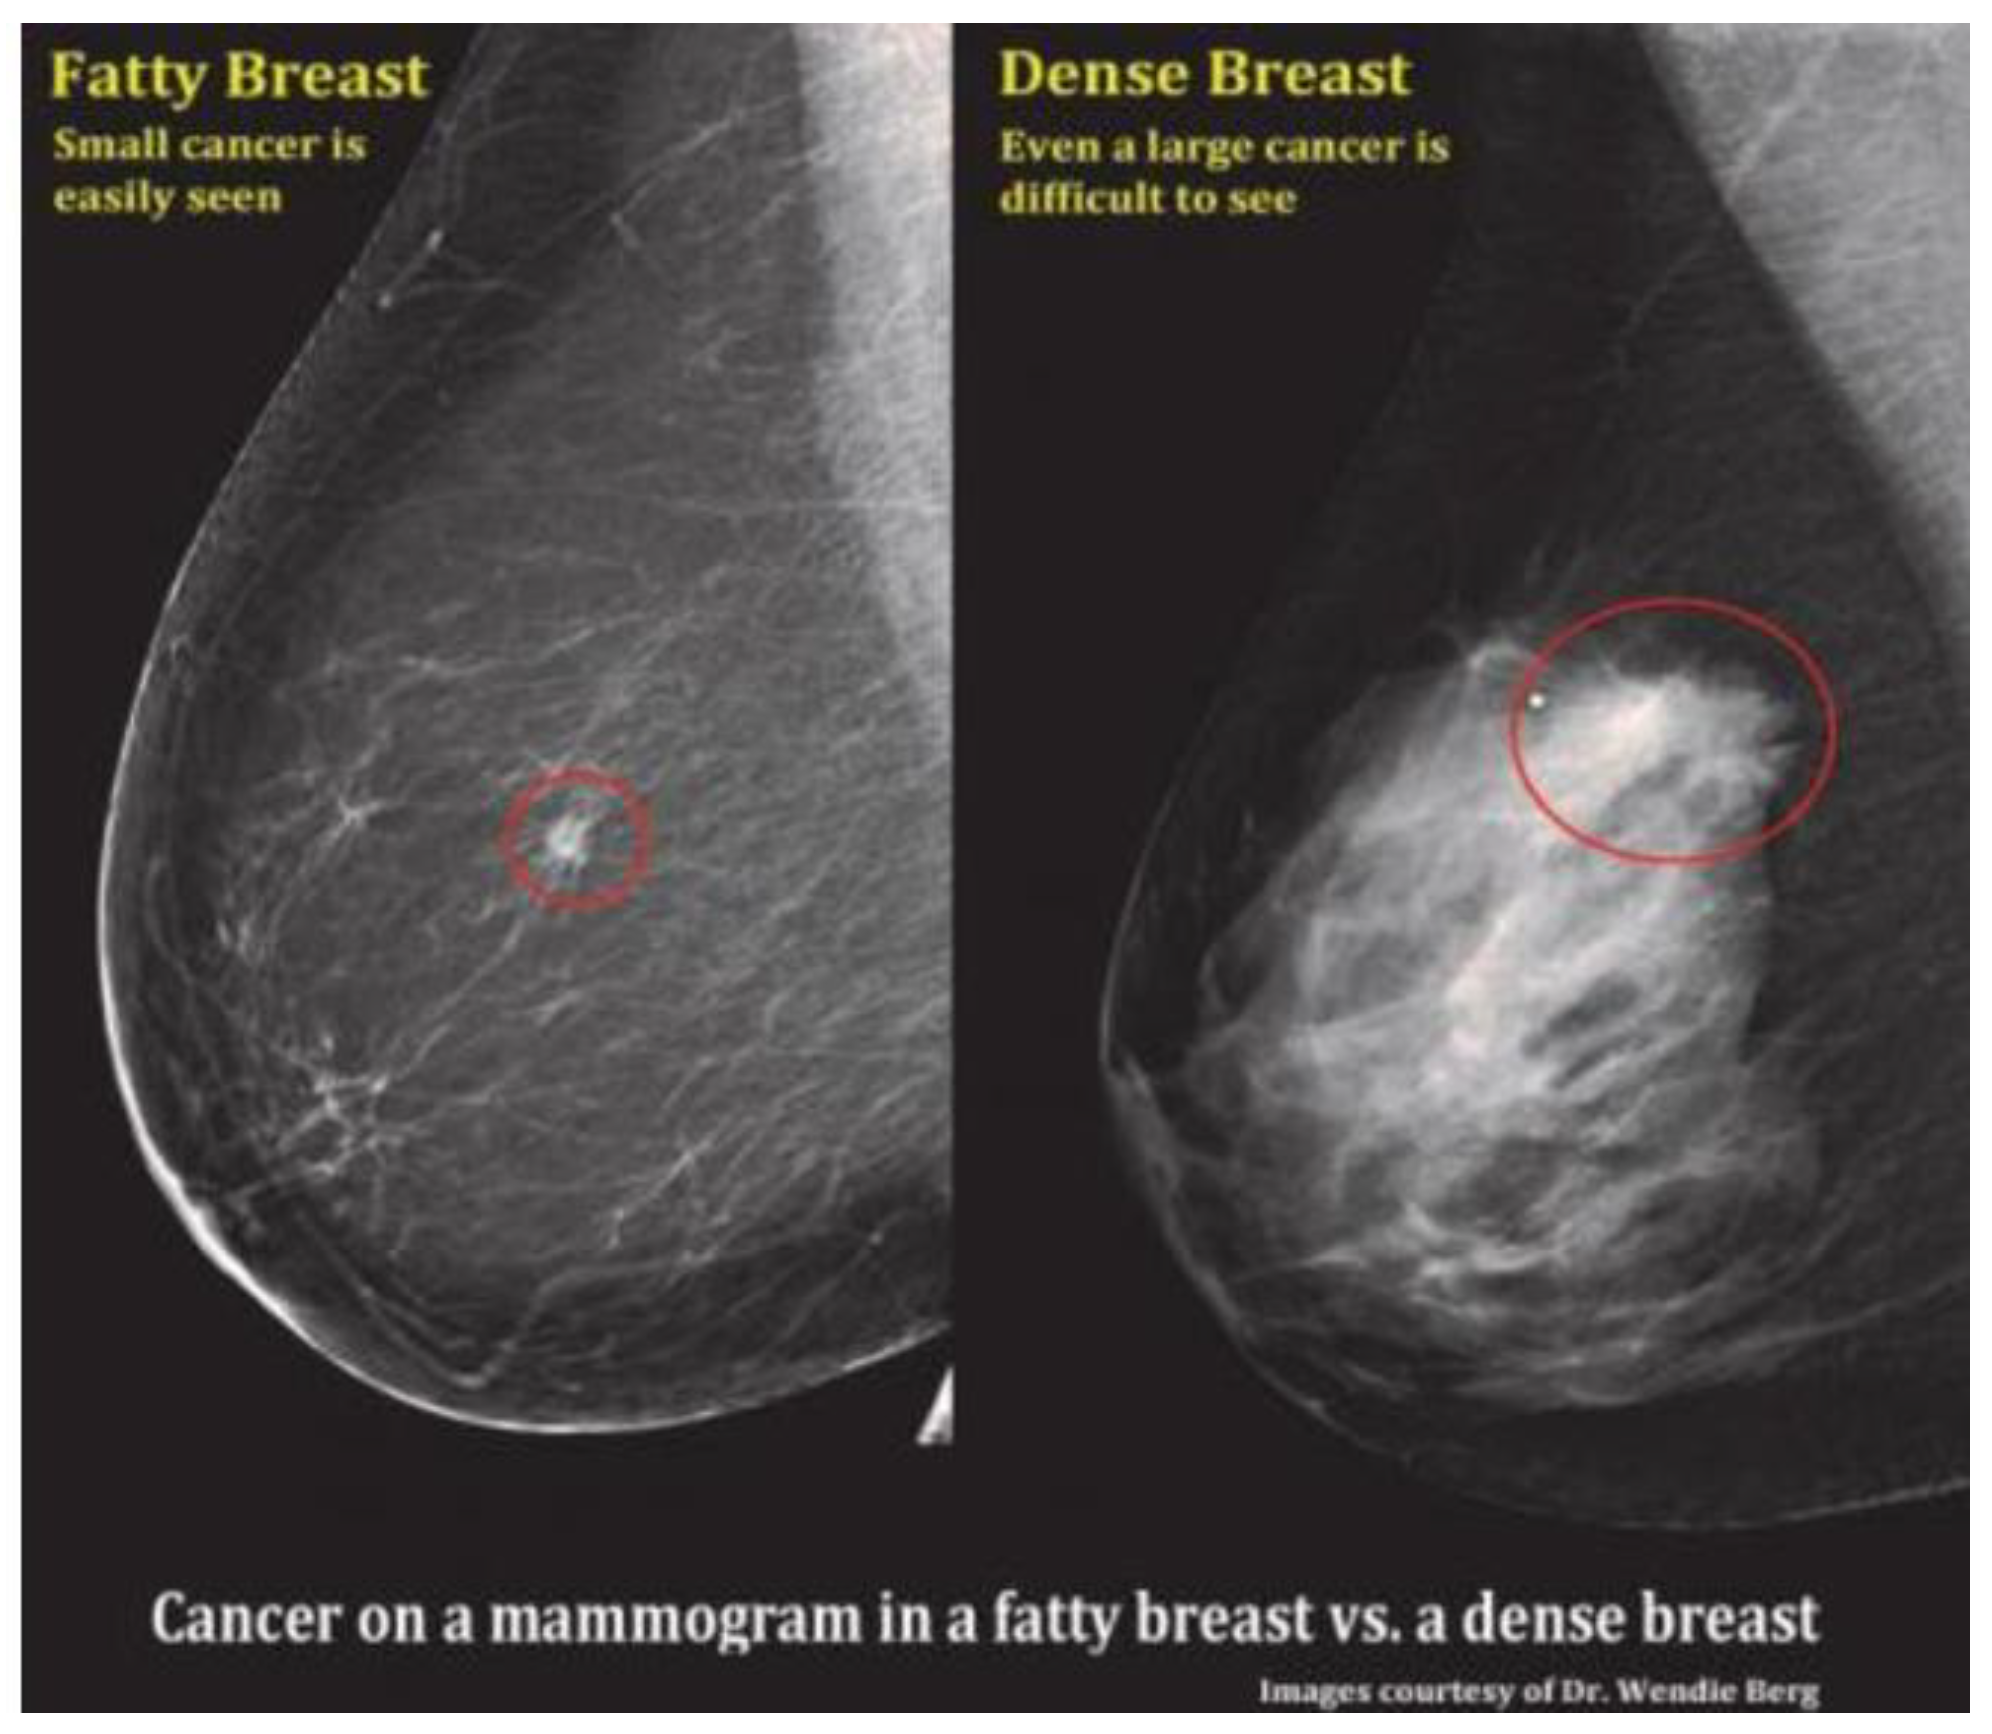

However, limitations arise with MAM, especially in cases involving dense breasts or breast implants, including silicone [24], which can complicate visual interpretation and lead to errors of omission, potentially resulting in the oversight of certain cancers [25] as shown in Figure 1. Despite technological advancements, high rates of false negatives and false positives have remained prevalent [26], contributing to overdiagnosis, patient anxiety, and the potential for radiation-induced harm [27]. False-negative rates for MAM have been reported to range widely, from 8.6% to as high as 43.6%, and between 10% to 30% in various studies [28], highlighting a critical limitation of this modality [28,29].

Figure 1. Mammographic comparison of dense vs. fatty breast tissue highlighting how increased density can mask potential cancers. In such cases, ultrasound may aid in detection [34].